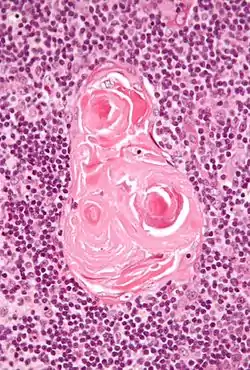

In the medulla, the network of epithelial cells is coarser than in the cortex, and the lymphoid cells are relatively fewer in number.[1] Concentric, nest-like bodies called Hassall's corpuscles (also called thymic corpuscles) are formed by aggregations of the medullary epithelial cells.[3] These are concentric, layered whorls of epithelial cells that increase in number throughout life.[1] They are the remains of the epithelial tubes, which grow out from the third pharyngeal pouches of the embryo to form the thymus.[6]

Micrograph showing a lobule of the thymus. The cortex (deeper purple area) surrounds a less dense and lighter medulla.

Micrograph showing a lobule of the thymus. The cortex (deeper purple area) surrounds a less dense and lighter medulla. Micrograph showing a Hassall's corpuscle, found within the medulla of the thymus.

Micrograph showing a Hassall's corpuscle, found within the medulla of the thymus.